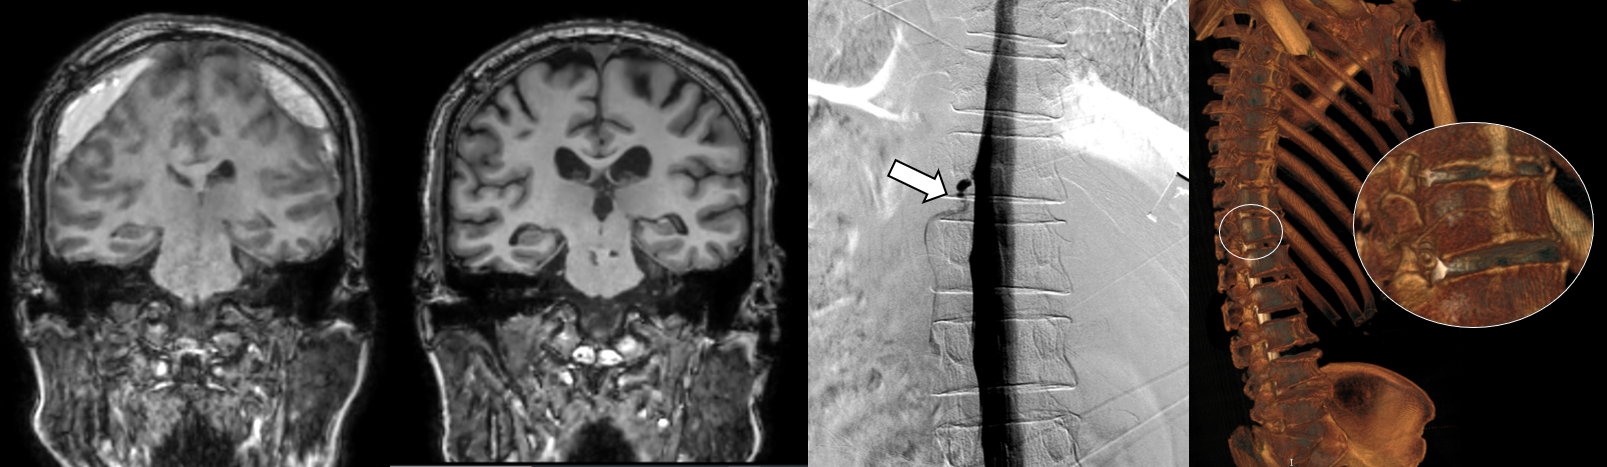

세브란스병원은 최근 DSM을 국내 최초로 도입해 이와 같은 기존 진단법의 한계를 극복했다. DSM(Digital Subtraction Myelography, 디지털 감산 척수조영술)은 척수에 조영제를 주입하고 모니터 화면으로 뇌척수액의 흐름을 실시간으로 확인할 수 있다. 이를 통해 뇌척수액이 새나가는 구멍을 정확하게 찾아낼 수 있게 됐다.

DSM과 더불어 세브란스병원이 함께 진행 중인 측위 CT 척수 조영술까지, 모두 뇌척수액 정맥 누공을 진단할 수 있는 최신 기법이다.

하우석 교수는 “자발성 두개내압 저하증과 특별한 외상이 없이 발생하는 경막하출혈의 원인 중 하나였던 뇌척수액 척수 누공은 두통, 인지능력 저하 등 심각한 고통을 일으키지만, 기존 진단법으로는 원인 규명이 쉽지 않던 상황”이라며 “세브란스병원이 도입한 DSM과 측위 CT 척수 조영술로는 척수액 누출이 발생하는 지점을 정확히 찾아내 치료할 수 있다”고 말했다.

[사진] (왼쪽) DSM으로 확인한 누공 위치, (오른쪽) 측위 CT 척수 조영술로 확인한 뇌척수액 정맥 누공 3D 영상